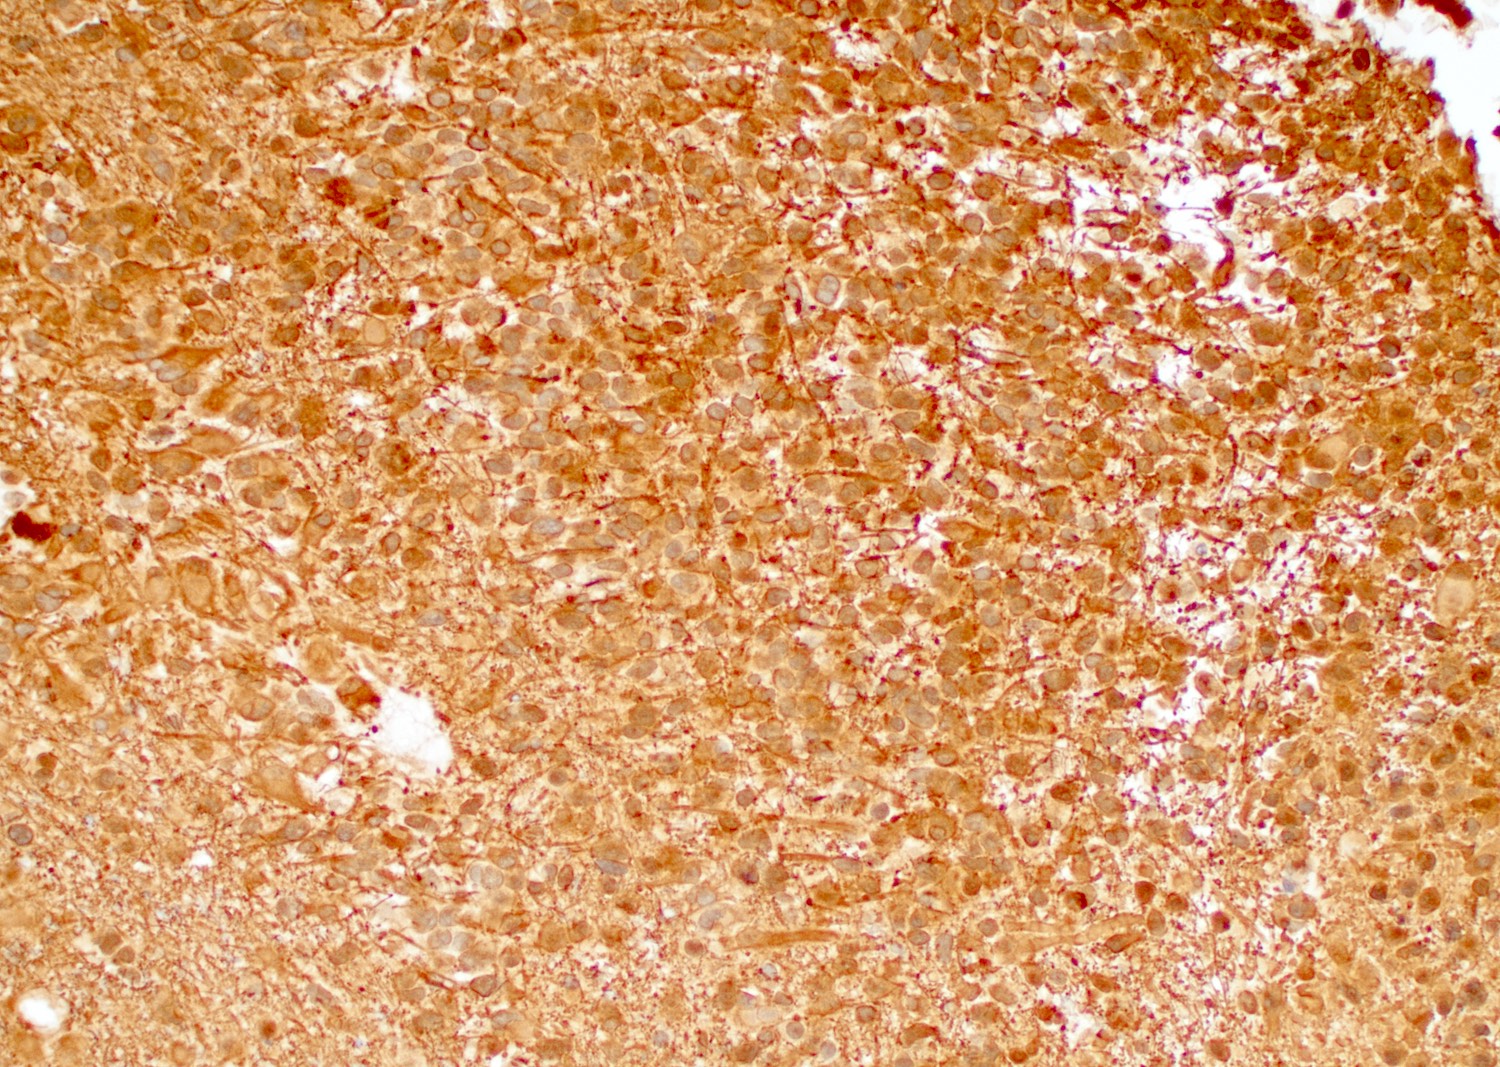

Positive stains

- GFAP, Olig2, S100

- GFAP may be lost in GBMs with sarcomatoid or primitive neuronal components

- Cytokeratin AE1 / AE3 may cross react with glial filaments (Pathol Oncol Res 2015;21:817)

- ATRX and H3K27 trimethylation usually retained

- EGFR (Indian J Med Res 2017;146:738)

Microscopic (histologic) images

Contributed by Bharat Ramlal, M.D. and Meaghan Morris, M.D., Ph.D.